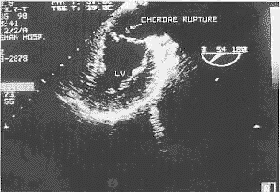

图1 二尖瓣后叶脱垂伴腱索断裂声像图,术前彩色多普勒血流显像示重度二尖瓣反流(LV-左室)